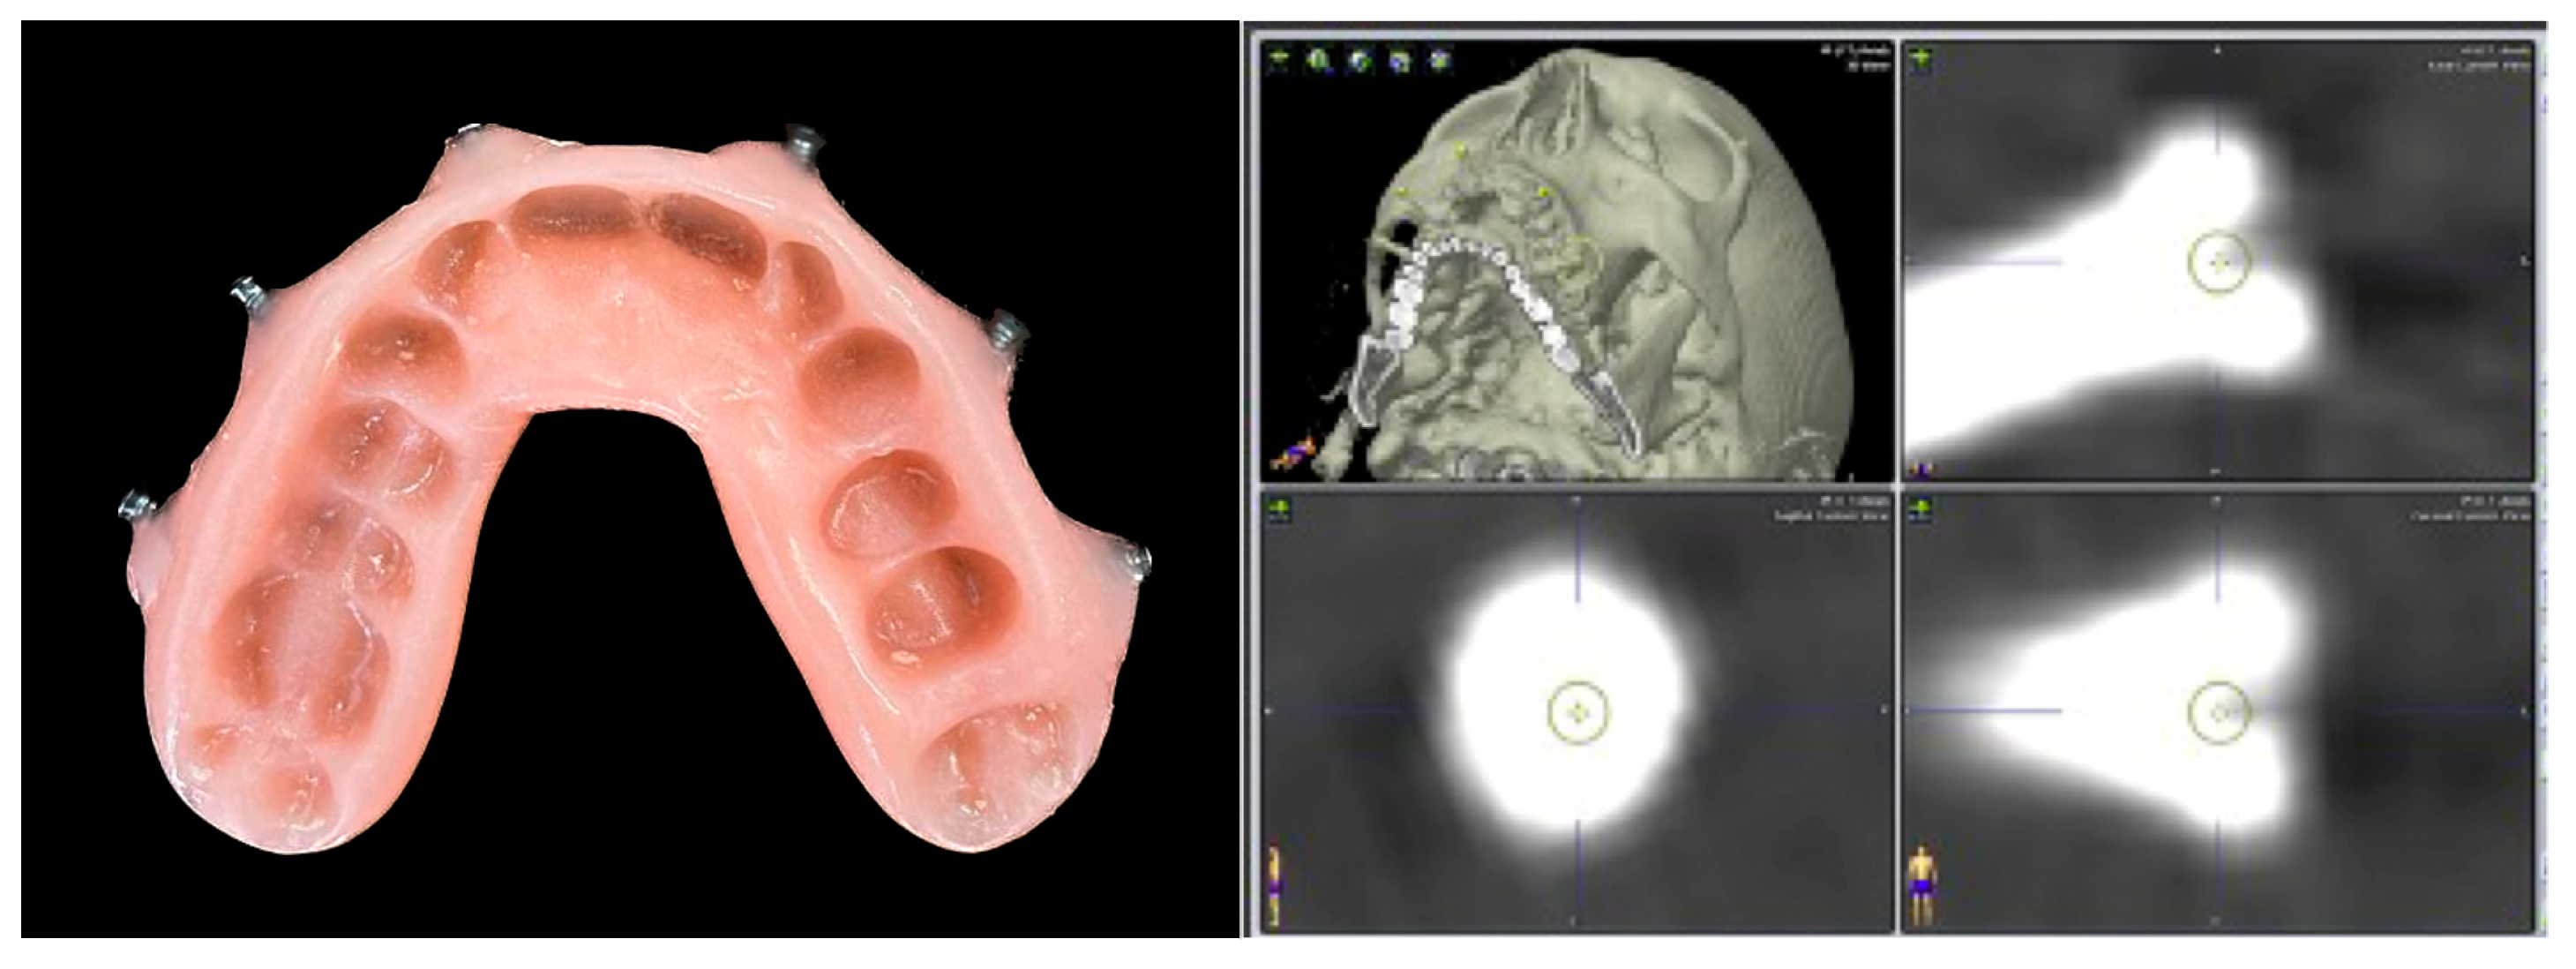

- Non-invasive fiducial markers: specific occlusal dental splints in which radiopaque landmarks are placed in such a way that they can be worn during the CT scan acquisition and used as non-invasive fiducial markers. It is an easy technique, but it requires the additional time to fabricate the splint. It cannot be used in edentulous patients, and its accuracy tends to be reduced above the plane passing through the orbital floor. The splint can be safely removed after registration and re-used during surgery and if the recording has to be repeated to verify the post-operative accuracy.